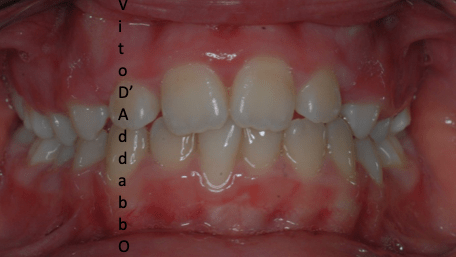

In alcune malocclusioni i denti superiori non coprono adeguatamente quelli inferiori con la presenza in alcuni casi di una beanza fra le due arcate. Questo può essere dovuto ad abitudini viziate come il succhiamento del dito, una deglutizione scorretta, una postura della lingua alterata o un problema scheletrico. In questo esempio il problema è associato ad una terza classe scheletrica.

prima